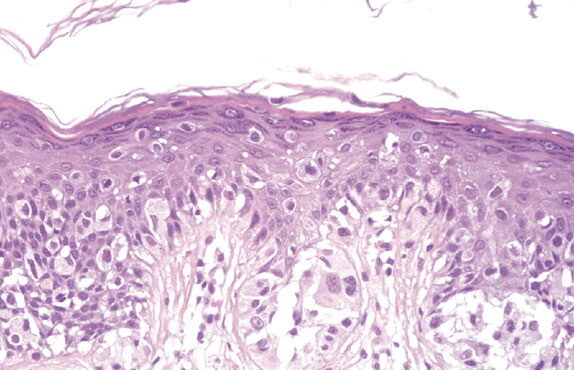

By Dr:jehad April 23, 2026 melanoma-in-situ-on-sun-damaged-skin-of-a face melanoma-in-situ-on-sun-damaged-skin-of-a face Read More